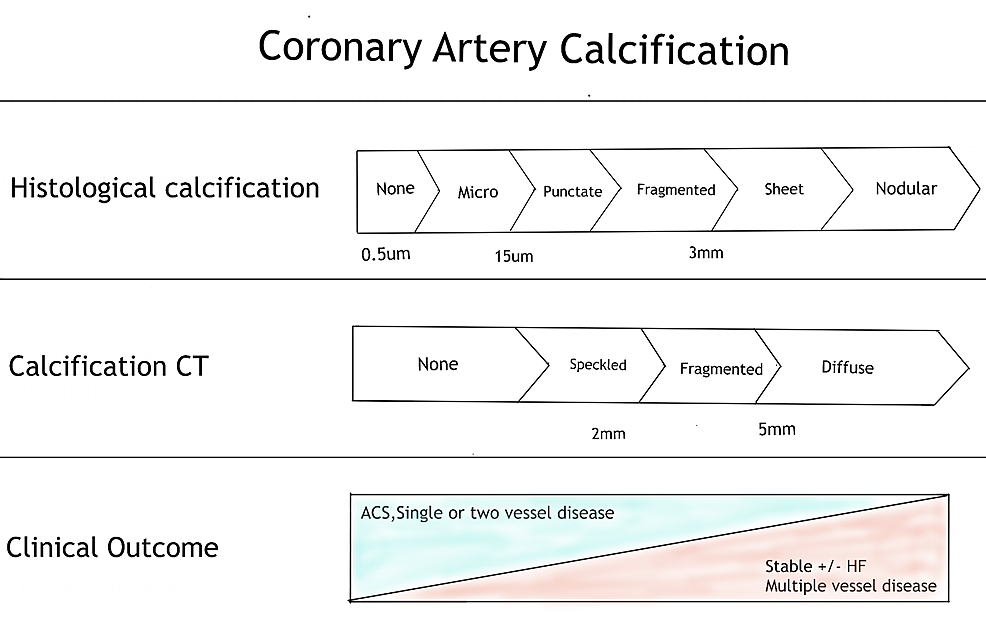

The Status Of Cardiac CT - Medical Forum

mforum.com.au

mforum.com.au

ct cardiac flow prognostic